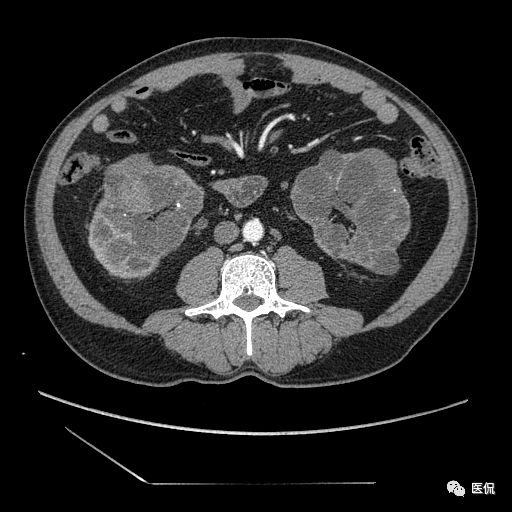

双肾实质可见多发囊性密度灶,其内密度不均匀,并可见钙化灶,增强扫描未见明显强化灶。肾周脂肪间隙清晰,与邻近组织分界清楚。

多囊肾的 CT 表现主要表现为双肾增大,轮廓光滑或有分叶,肾实质内多个大小不等的囊肿呈蜂窝状,多呈水样低密度,增强扫描囊肿本身无强化,而囊肿间正常肾组织增强,对比明显。当囊肿张力过高,使囊壁上毛细血管牵拉破裂出血时,表现为囊肿内稍高密度影,随访CT 值减低。囊壁钙化,表现为点线状高密度影像,随访CT值无变化。有文献报道约 30%病例可并发多囊肝或多囊胰。